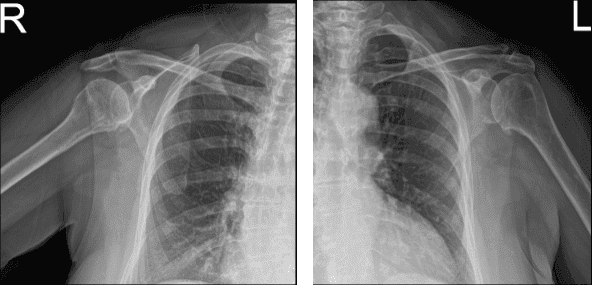

Patient presents today with bilateral shoulder pain. She is 69 year-old, nothing remembers involving in any form of accident. Patient has undergone physical therapy and still experiences the pain. She explains that both shoulders have been hurting for almost 4 years now.

Her pain and restriction of movement are unchanged. She brought her X-ray results today and reviewed them. Her bilateral shoulder showed the impression of mild acromioclavicular and glenohumeral degenerative changes.

MRI of Left and Right Shoulder

To understand better the condition of her shoulders we decided to take an MRI. Left shoulder MRI impression as follows: Supraspinatus tendinosis with low-grade partial-thickness articular sided tearing. Degeneration of the acromioclavicular and glenohumeral joints.

Truncation of the free edge posterior superior glenoid labrum. Moderate glenohumeral joint effusion. Tendinosis and tenosynovitis of the long of the biceps tendon. Right MRI impression as follows: Degenerative changes of the acromioclavicular and glenohumeral joints. Supraspinatus as with high-grade partial-thickness articular sided tearing. Tear of the posterior superior labrum.